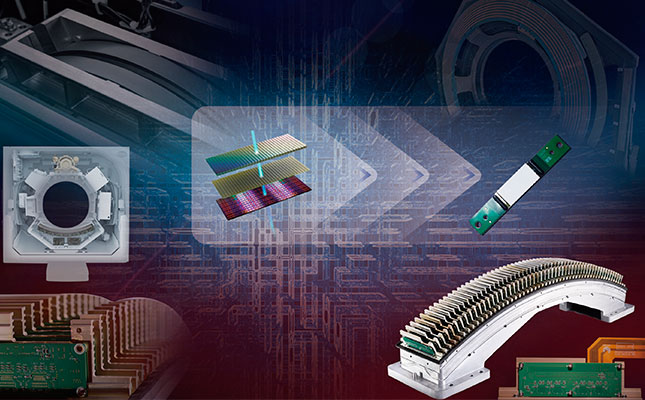

Новое поколение керамических детекторов Vision HD Detector

В компьютерных томографах Insitum используются твердотельные детекторы нового поколения из оксисульфида гадолиния. Применение в качестве матрицы соединений гадолония позволяет снизить лучевую нагрузку и уменьшить концентрацию контрастного вещества без ущерба качеству изображения. Точность сканирования гарантируется такими свойствами керамики, как поглощение энергии в широком диапазоне, высокая чувствительность к затухающим излучениям, большой коэффициент сорбции рентгеновских лучей.

32-рядная детекторная решетка

32-рядная детекторная система, независимо разработанная компанией SinoVision, позволяет осуществлять непрерывный сбор перекрывающихся данных о каждой анатомической детали и получать данные диплоидного детектора, что позволяет избежать искажений мягких тканей и на границе раздела костной ткани и воздуха и добиться непревзойденного качества изображения. Новое поколение редкоземельных керамических детекторов может обеспечить сверхвысокую эффективность поглощения, сверхнизкий электронный шум и высокое качество изображения, точно воспроизводя каждое значение вокселя изображения и достигая высокого изотропного разрешения.

Настоящий 32-рядный физический детекторный модуль с воссозданием 32 изображений за один оборот. Качество изображения в формате Full HD, с высокой скоростью и тонким срезом.

Удвоенное качество с 32-срезным детектором

КТ Insitum 32 использует физический 32-рядный равнопиксельный трехмерный детектор. По сравнению с традиционным 16-срезным КТ, он может выполнять обследование за то же время и при том же расходе энергии. Сверхвысокая изотропия достигается за счет оптимизированного размера кубических пикселей - 0,625 мм, который гарантирует, что изображения не будут искажаться при наблюдении под любым углом.

Конструкция равноудаленного детектора размером 32x0,625 мм в сочетании с получением и реконструкцией данных в режиме реального времени с помощью двухканального DAS и технологии переключения рентгеновских трубок позволяют получить действительно высокое разрешение, тонкий срез и быстрое сканирование.